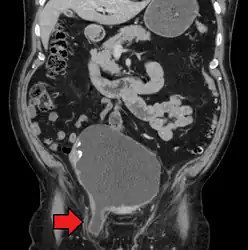

Medical imaging

A physician may diagnose an inguinal hernia, as well as the type, from medical history and physical examination.[11] For confirmation or in uncertain cases, medical ultrasonography is the first choice of imaging, because it can both detect the hernia and evaluate its changes with for example pressure, standing and Valsalva maneuver.[12]

When assessed by ultrasound or cross sectional imaging with CT or MRI, the major differential in diagnosing indirect inguinal hernias is differentiation from spermatic cord lipomas, as both can contain only fat and extend along the inguinal canal into the scrotum.[13]

On axial CT, lipomas originate inferior or lateral to the cord, and are located inside the cremaster muscle, while inguinal hernias lie anteromedial to the cord and are not intramuscular. Large lipomas may appear nearly indistinguishable as the fat engulfs anatomic boundaries, but they do not change position with coughing or straining.[13]

A frontal view of an incarcerated inguinal hernia (on the patient's left side) with dilated loops of bowel above. -